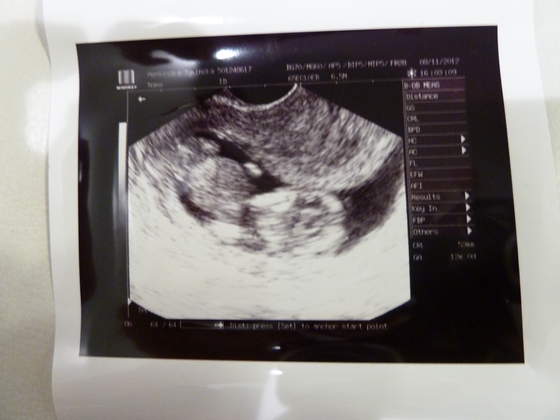

Wszystko w porządku, maluch ma ponad 5cm długości, serducho bije 166/min. To była normalna wizyta, więc bez innych szczegółów - genetyczne USG za tydzień.

A to Maluch:

Usg z poniedzialku, wszystko ok, przeziernosc 1,3 mm